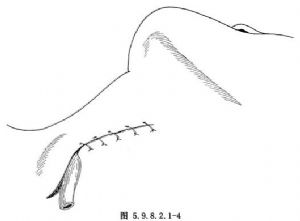

食管穿孔治療的成敗取決於穿孔部位、裂口大小、確診時間及治療措施是否得當。穿孔時間超過24h者,其傷死率比早期治療的高3倍多。食管穿孔治療方案的制定、手術方法的選擇應根據具體情況做出。總的原則是:①消除污染來源;②充分引流;③抗生素應用;④維持水電解質平衡及足夠的營養。